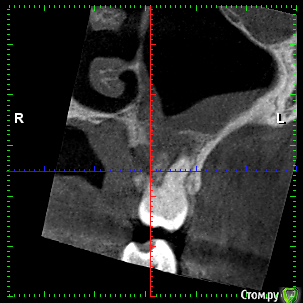

rezo47 Опубликовано 24 сентября, 2015 Автор Поделиться Опубликовано 24 сентября, 2015 Только пришло КТ, вопросов стало больше((( Ссылка на комментарий

kriokov Опубликовано 24 сентября, 2015 Поделиться Опубликовано 24 сентября, 2015 27 удаляйте Ссылка на комментарий

rezo47 Опубликовано 24 сентября, 2015 Автор Поделиться Опубликовано 24 сентября, 2015 (изменено) 27 удаляйтеДиагноз? Изменено 24 сентября, 2015 пользователем rezo47 Ссылка на комментарий

kladoffka Опубликовано 24 сентября, 2015 Поделиться Опубликовано 24 сентября, 2015 Хр пр 2 Ссылка на комментарий

kriokov Опубликовано 24 сентября, 2015 Поделиться Опубликовано 24 сентября, 2015 Диагноз?что хотите, на выбор(например- "не жилец" ) Ссылка на комментарий

red_butler Опубликовано 24 сентября, 2015 Поделиться Опубликовано 24 сентября, 2015 сначала гистология, потом лечение Ссылка на комментарий